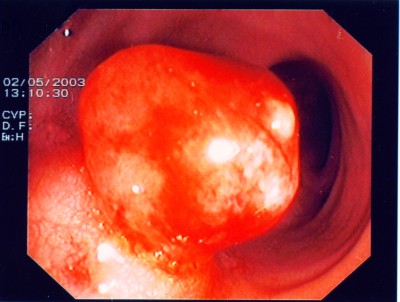

Großer Polyp des Dickdarmes